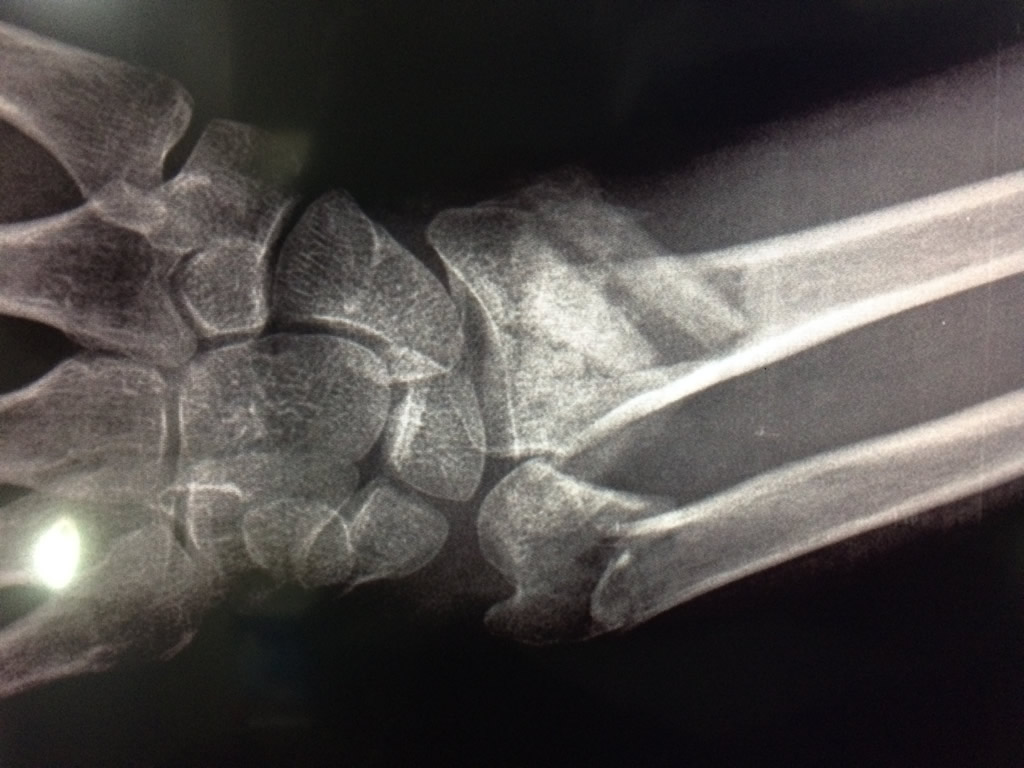

Cirugías de Codo - Cirugías de Muñecas y Manos

Los procedimientos más comunes en cirugía de la mano son aquellos destinados a reparar traumatismos, incluyendo lesiones de tendones, nervios, vasos sanguíneos, y articulaciones; huesos fracturados; y quemaduras, cortes, y otros daños de la piel.